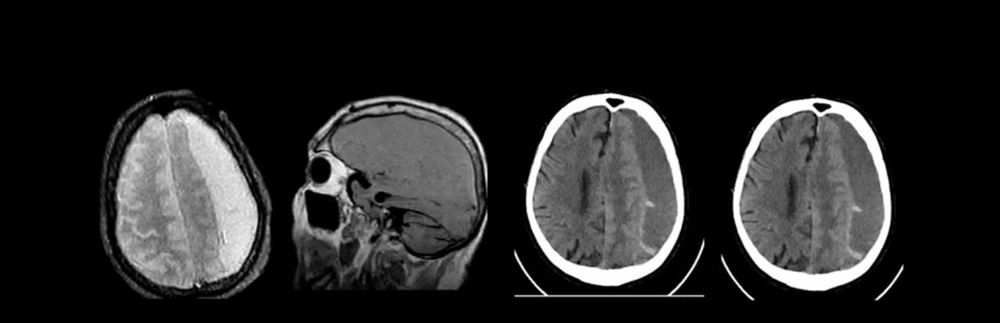

ЕХО-ЕС – при відсутності КТ, МРТ. Провідними методами діагностики є КТ і МРТ головного мозку. Комп’ютерна томографія в основному проводиться в гострий період травми тому, що краще візуалізується скупчення крові між дуральною оболонкою та мозком.

При хронічній субдуральній гематомі для діагностики перевагу віддають МРТ.